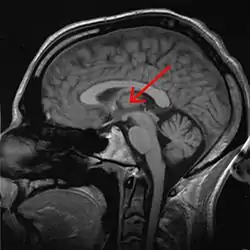

![]() Thalamus marked (MRI cross-section) | |

The thalamus (pl.: thalami; from Greek θάλαμος, "chamber")[1] is a large mass of gray matter located in the dorsal part of the diencephalon (a division of the forebrain). Nerve fibers project out of the thalamus to the cerebral cortex in all directions, known as the thalamocortical radiations, allowing hub-like exchanges of information. It has several functions, such as the relaying of sensory signals, including motor signals to the cerebral cortex[2][3] and the regulation of consciousness, sleep, and alertness.[4]

Anatomically, it is a paramedian symmetrical structure of two halves (left and right), within the vertebrate brain, situated between the cerebral cortex and the midbrain. It forms during embryonic development as the main product of the diencephalon, as first recognized by the Swiss embryologist and anatomist Wilhelm His Sr. in 1893.[5]

The thalamus is a paired structure of gray matter about four centimetres long, located in the forebrain which is superior to the midbrain, near the center of the brain with nerve fibers projecting out to the cerebral cortex in all directions. The medial surface of the thalamus constitutes the upper part of the lateral wall of the third ventricle, and is connected to the corresponding surface of the opposite thalamus by a flattened gray band, the interthalamic adhesion. The lateral part of the thalamus is the phylogenetically newest part of the thalamus (neothalamus), and includes the lateral nuclei, the pulvinar and the medial and lateral geniculate nuclei.[6][7] There are areas of white matter in the thalamus including the stratum zonale that covers the dorsal surface and the external and internal medullary laminae. The external lamina covers the lateral surface and the internal lamina divides the nuclei into anterior, medial, and lateral groups.[8]